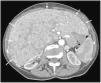

Gastroenterología y Hepatología Hepatomegaly from pancreatic cancer metastasis

Hepatomegaly from pancreatic cancer metastasis

Hepatomegalia por metástasis de cáncer de páncreas